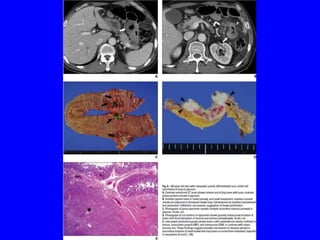

• Metastatic breast cancer with GIT involvement represents evidence

of a systemic disease,with great variability, including lesions with a

benign appearance but also diffusely infiltrative lesions&localized

tumor formation with nodules/or ulceration.

Diagnosis:

• Can be difficult due to an often prolonged tumor-free interval &

benign appearance of the lesions &gastric metastasis may

occasionally mimic a gastric primary.

• Stomach is the most frequent GIT site for metastatic breast cancer.

• The most characteristic endoscopic finding of metastatic lobular

breast carcinoma is a linitis-plastica-like appearance,showing tumor

infiltration along the stomach wall with mural thickening of the

involved segment & submucosal infiltration,makes the diagnosis

difficult on endoscopic & imaging exams.

• Advances in imaging techniques like CT scan &EUS with guided

biopsy have aided confirmation of the diagnosis.